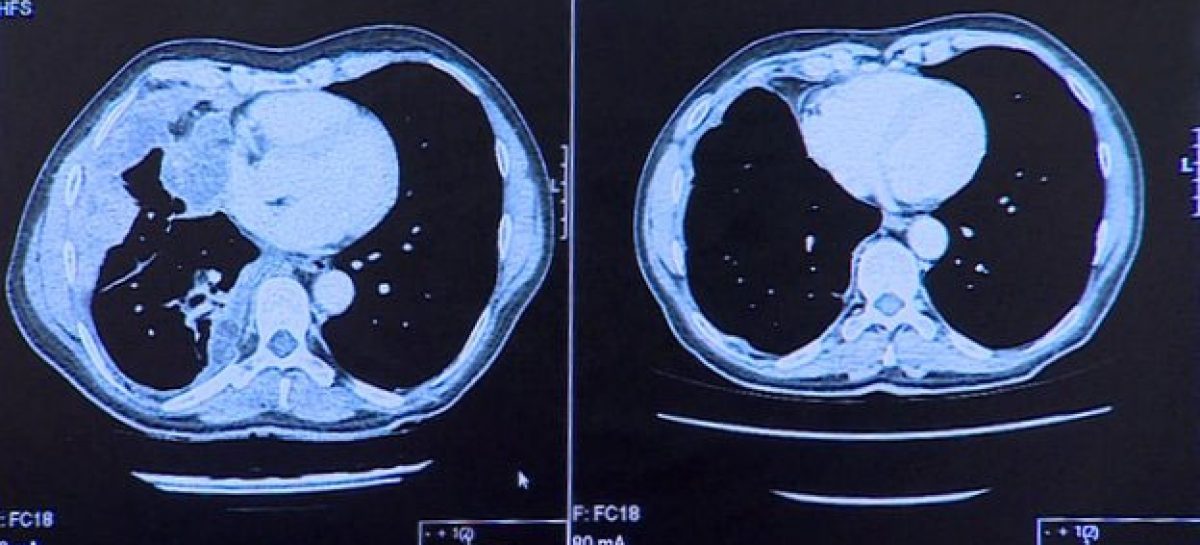

Exames em seu pulmões (como mostram as imagens acima) revelam que, depois de apenas três doses, o remédio parece ter removido completamente o câncer do órgão.